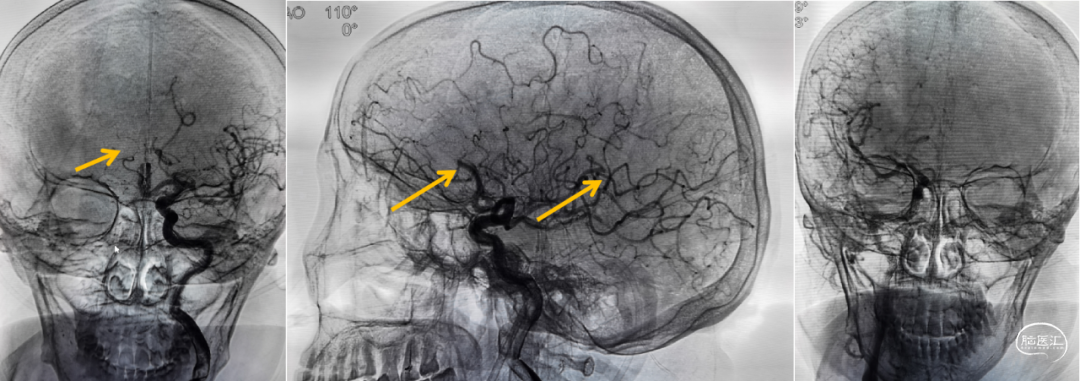

造影证实:双侧大脑前动脉均由左侧发出、双侧大脑前动脉栓塞、左侧大脑中动脉下干远端栓塞。